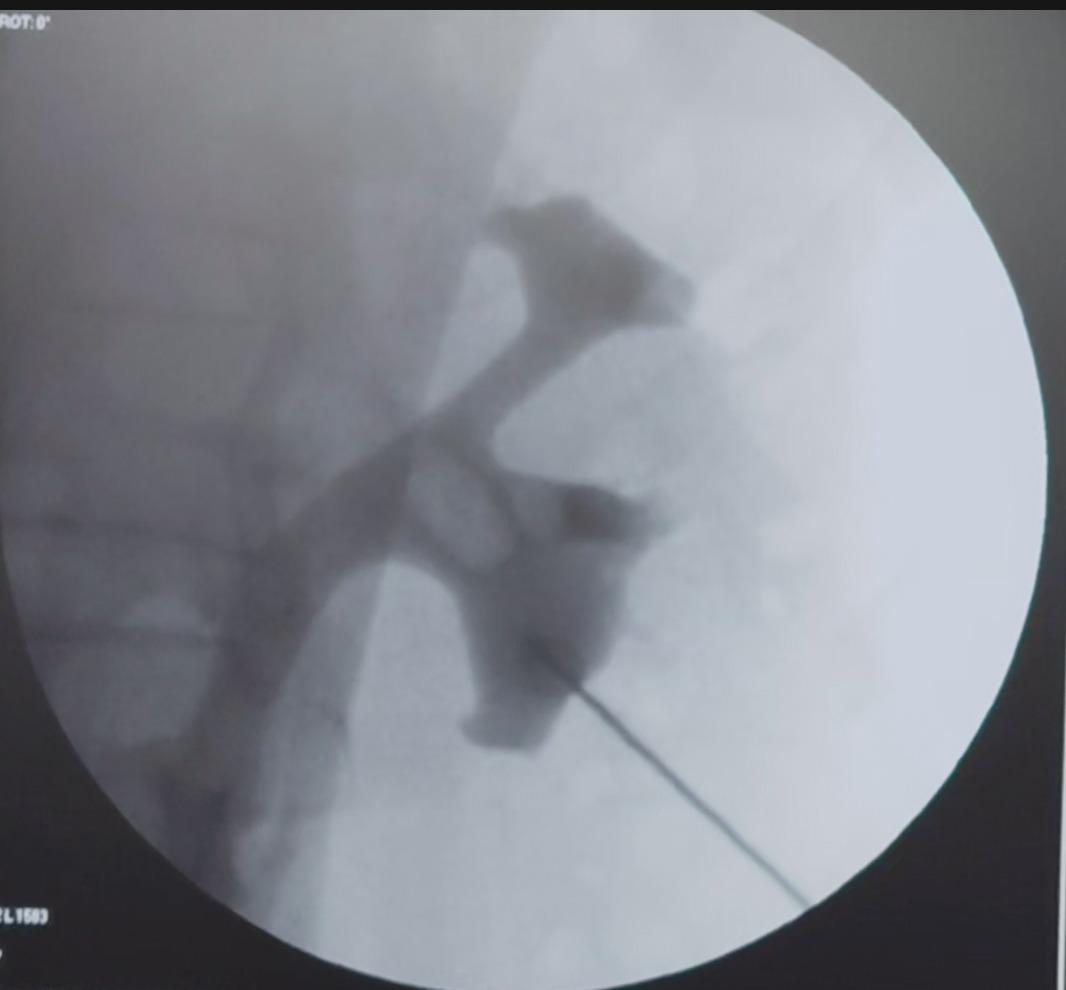

🔹 PCNL